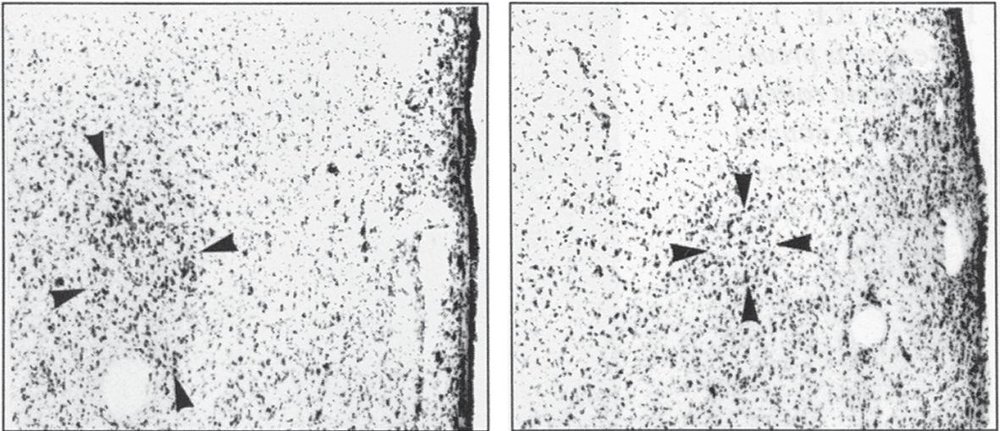

Во-первых, регион INAH 3 у гетеросексуальных мужчин почти в два раза больше по сравнению с геями (с момента публикации исследования был только один его успешный повтор). Во-вторых, гипоталамус у мужчин-геев и гетеросексуальных женщин реагирует на феромоны из мужского пота, а феромоны из женской урины вызывают реакцию только у центра обработки запахов. Влияние гипоталамуса на этом не заканчивается: в одном исследовании обнаружили, что у мужчин-геев он реагирует на флуоксетин, распространённый антидепрессант, совсем не так сильно, как у гетеросексуальных мужчин. По какой-то причине этому исследованию не придали значения, хотя оно может сильно повлиять на клиническую практику: если серотонергическая система (флуоксетин взаимодействует с серотонином) у геев работает по-другому, возможно, их надо по-другому лечить от депрессии?

Большой комок слева – это INH3 у гетеросексуальных мужчин, меньший комок справа — INH3 у гомосексуальных

Слева вверху – BNST гетеросексуального мужчины, справа вверху – женщины, слева внизу – гомосексуального мужчины, справа внизу – трансгендера М-Ж